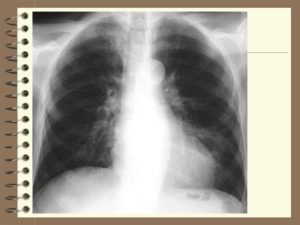

Кроме вышеописанных отклонений от нормы, в письменных заключениях врачей можно увидеть характеристики, которые могут стать признаками наличия патологии: корни легких уплотнены и расширены, тяжисты и усиленны.

Что значит, если корень легкого уплотнен? Чаще всего причиной становится отек бронхов, расширение сосудов или увеличение лимфатических узлов. Ткани корней уплотняются и расширяются синхронно, если корни легких только уплотнены – это значит, что в организме запущен хронический процесс. На рентгеновских снимках уплотненные корни имеют расплывчатые очертания и крупный размер.

Помимо ранее упомянутых новообразований, можно отметить следующие характеристики корней, которые обозначаются в письменных заключениях, являются отклонениями от нормы и могут быть признаками патологий: уплотненные, тяжистые и расширенные корни, также корни могут быть усилены.

Корни уплотнены и расширены

Обычно это происходит из-за отёка бронхов или крупных сосудов. А в некоторых случаях и из-за того, что происходит увеличение лимфоузлов.

Уплотнение и расширение ткани корней почти всегда происходит одновременно, если же корни только уплотнены, это говорит о хроническом процессе.

На снимке расширенные корни будут выглядеть менее чёткими, а также крупнее стандартных размеров.